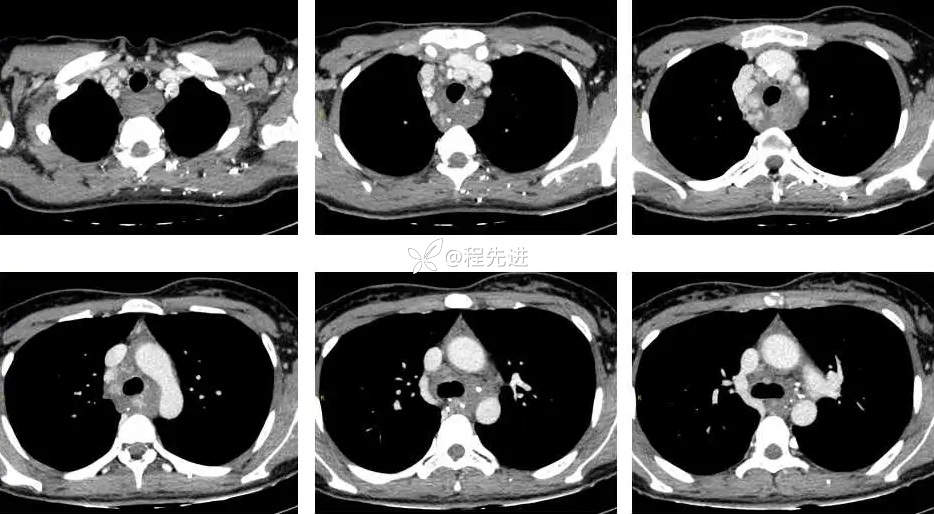

CT平扫+增强: